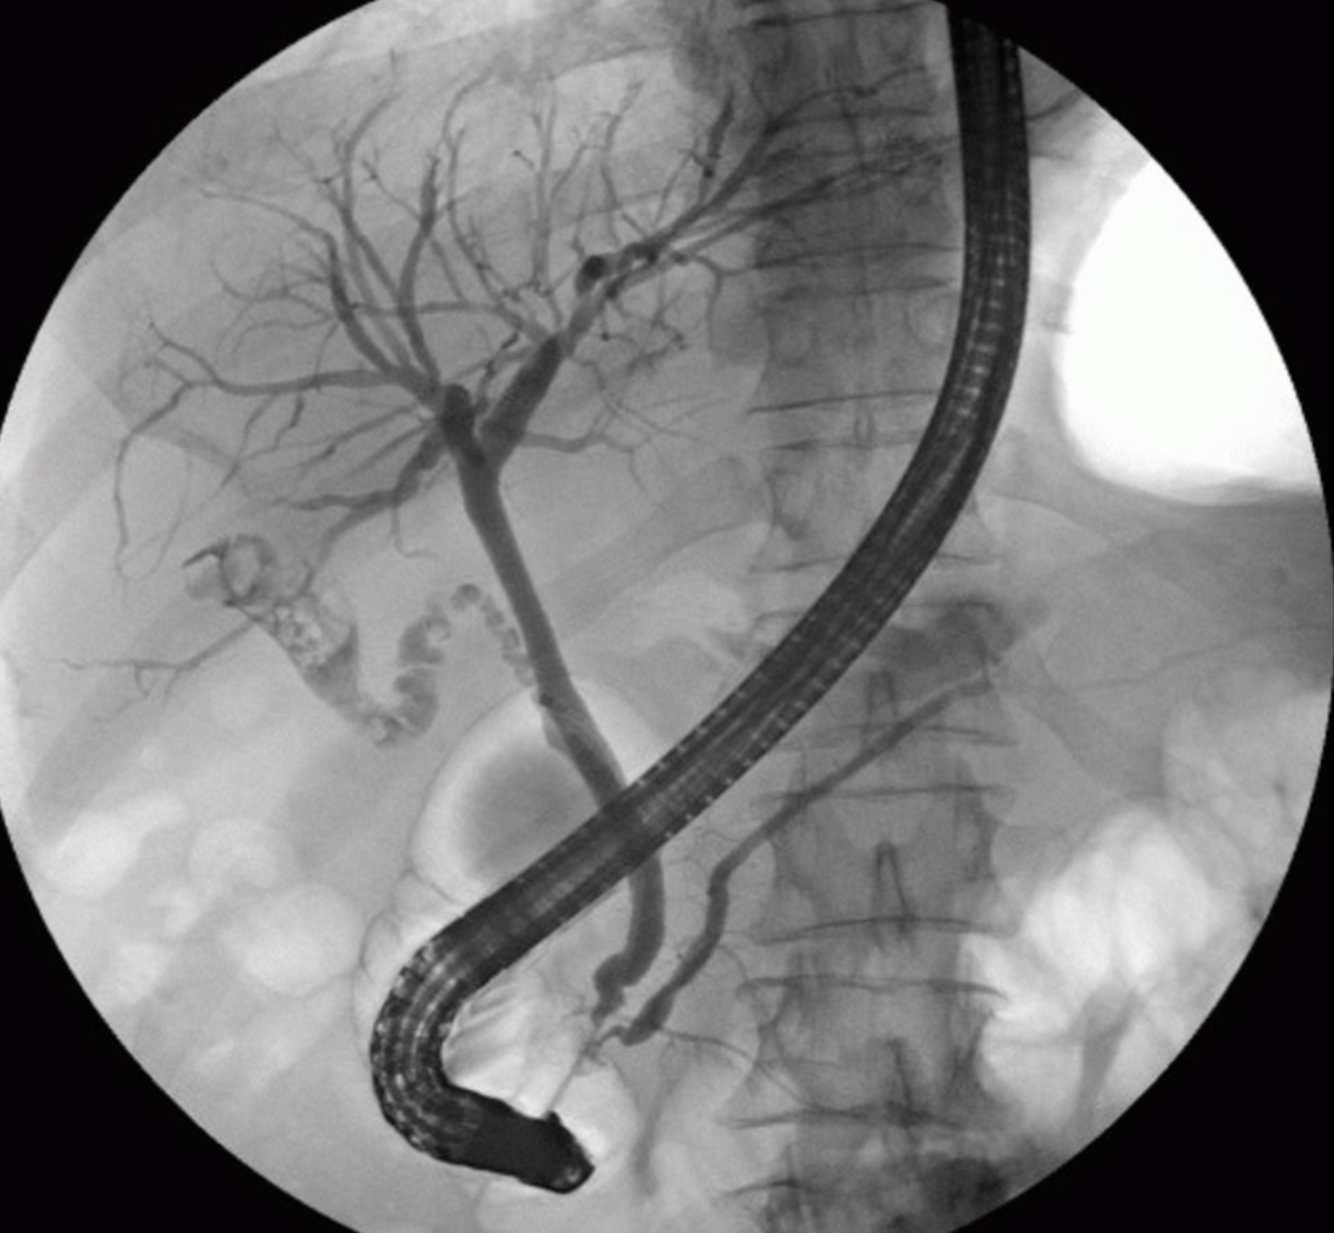

Cholangiopancréatographie rétrograde endoscopique (CPRE)

La pointe de l’endoscope (E) est située dans le duodénum au niveau de l’ampoule de Vater. L’amélioration du contraste permet de visualiser les voies biliaires hépatiques, les canaux hépatiques gauche et droit, le canal cystique (CD), la vésicule biliaire (G), le canal cholédoque (CBD) et le canal pancréatique (PD). Plusieurs défauts de remplissage (exemples indiqués par une superposition verte) peuvent être observés dans la vésicule biliaire et le canal cystique.

Cette constatation est le diagnostic de lithiase biliaire.